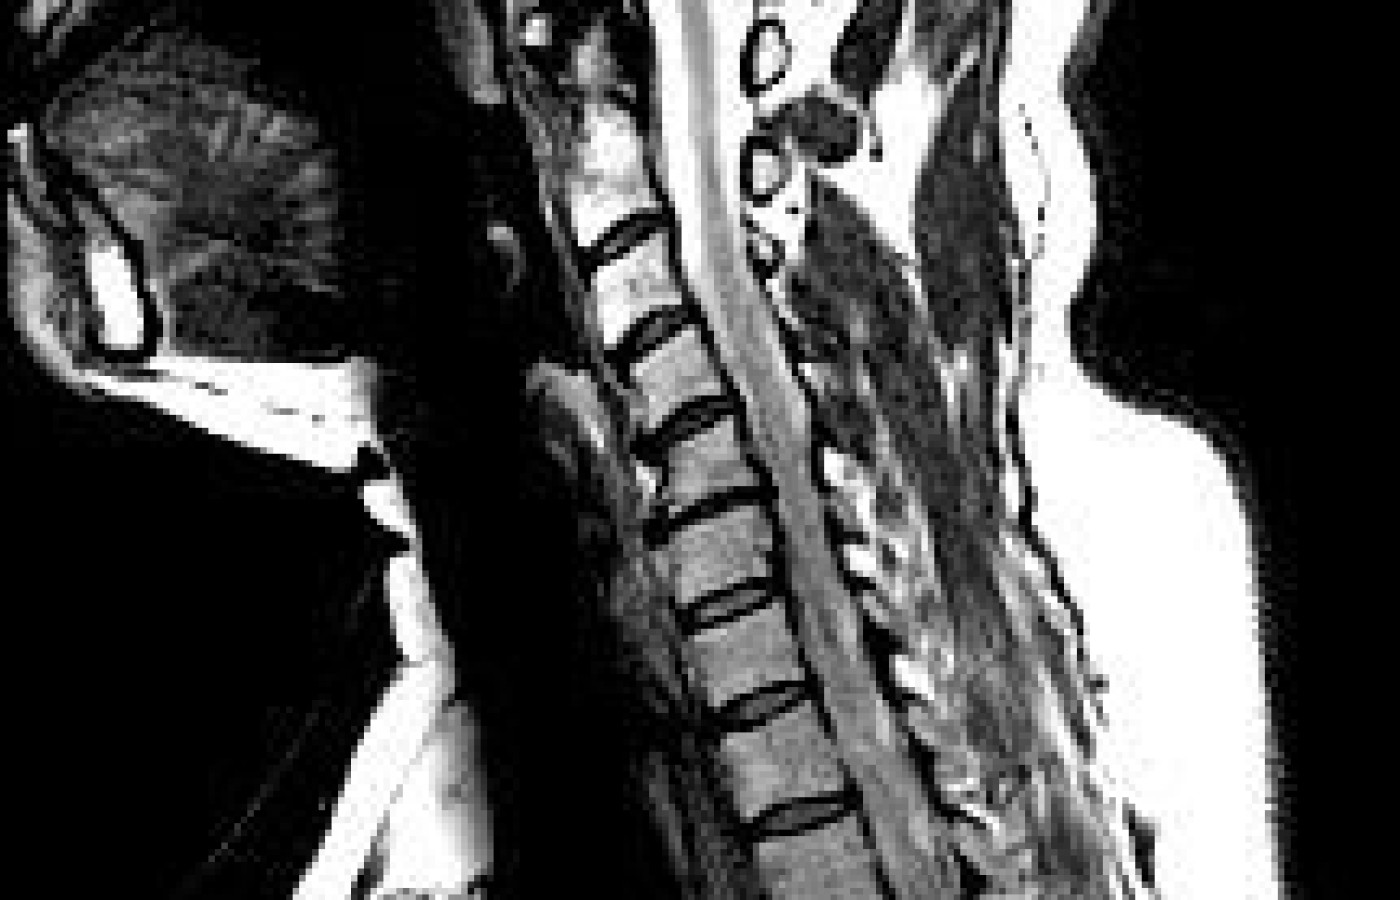

She hand-carried a current MRI of her cervical spine with her to my facility. These figures represent cervical Arthritis may affect the joints in the spine - joints that enable the body to bend and twist. Part of the problem may be the body's response to arthritis, which is to manufacture extra bone to stop joint movement. The extra bone is called a bone spur or bony overgrowth. In medical terms, the extra bone is called osteophytes, which may be found in areas affected by arthritis, such as the disc or joint spaces, where cartilage has deteriorated. The body's production of osteophytes is a futile attempt to stop the motion of the arthritic joint and deal with the degenerative process. The evidence of bony deposits can be found on X-ray (which allowed my initial cervical spondylosis impression). A bone spur may cause nerve impingement at the neuroforamen, as demonstrated by the signal degradation in Figure 3. Sensory symptoms include pain, numbness, burning, and pins and needles in the extremities below the affected spinal nerve root. Motor symptoms include muscle spasm, cramping, weakness, or loss of muscular control in a part of the body.

Based on the MRI of the cervical spine and the fact that the old condition of cervical spondylosis C4-6 remained, she was asked to be monitored by a neurologist until her neurosurgical cervical follow-up was obtained (3-4 months from the initial visit). This would afford case management of her hand numbness to hopefully full resolution, and hopefully full satisfaction of the patient that a left-sided carpal tunnel syndrome was primary causation.